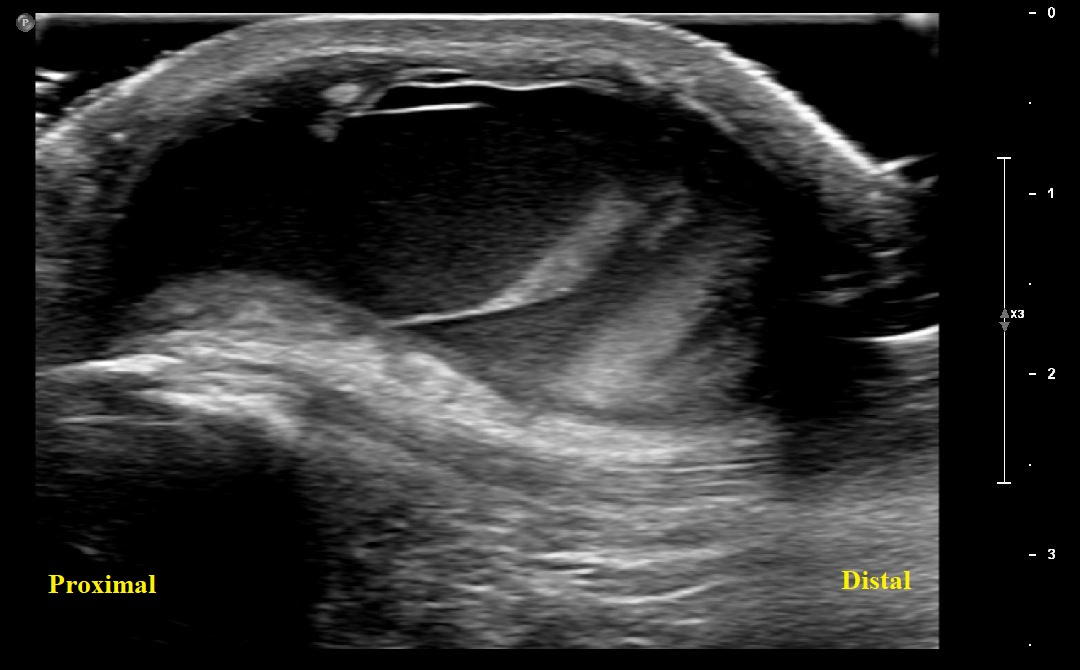

Short Axis view of proximal patellar tendon with overlying prepatellar bursal distension.

Long Axis view of Right Patella with overlying prepatellar bursal distension/bursitis. No fractures or cortical irregularities along patella.

Long Axis view of Right Patella with overlying prepatellar bursal distension.